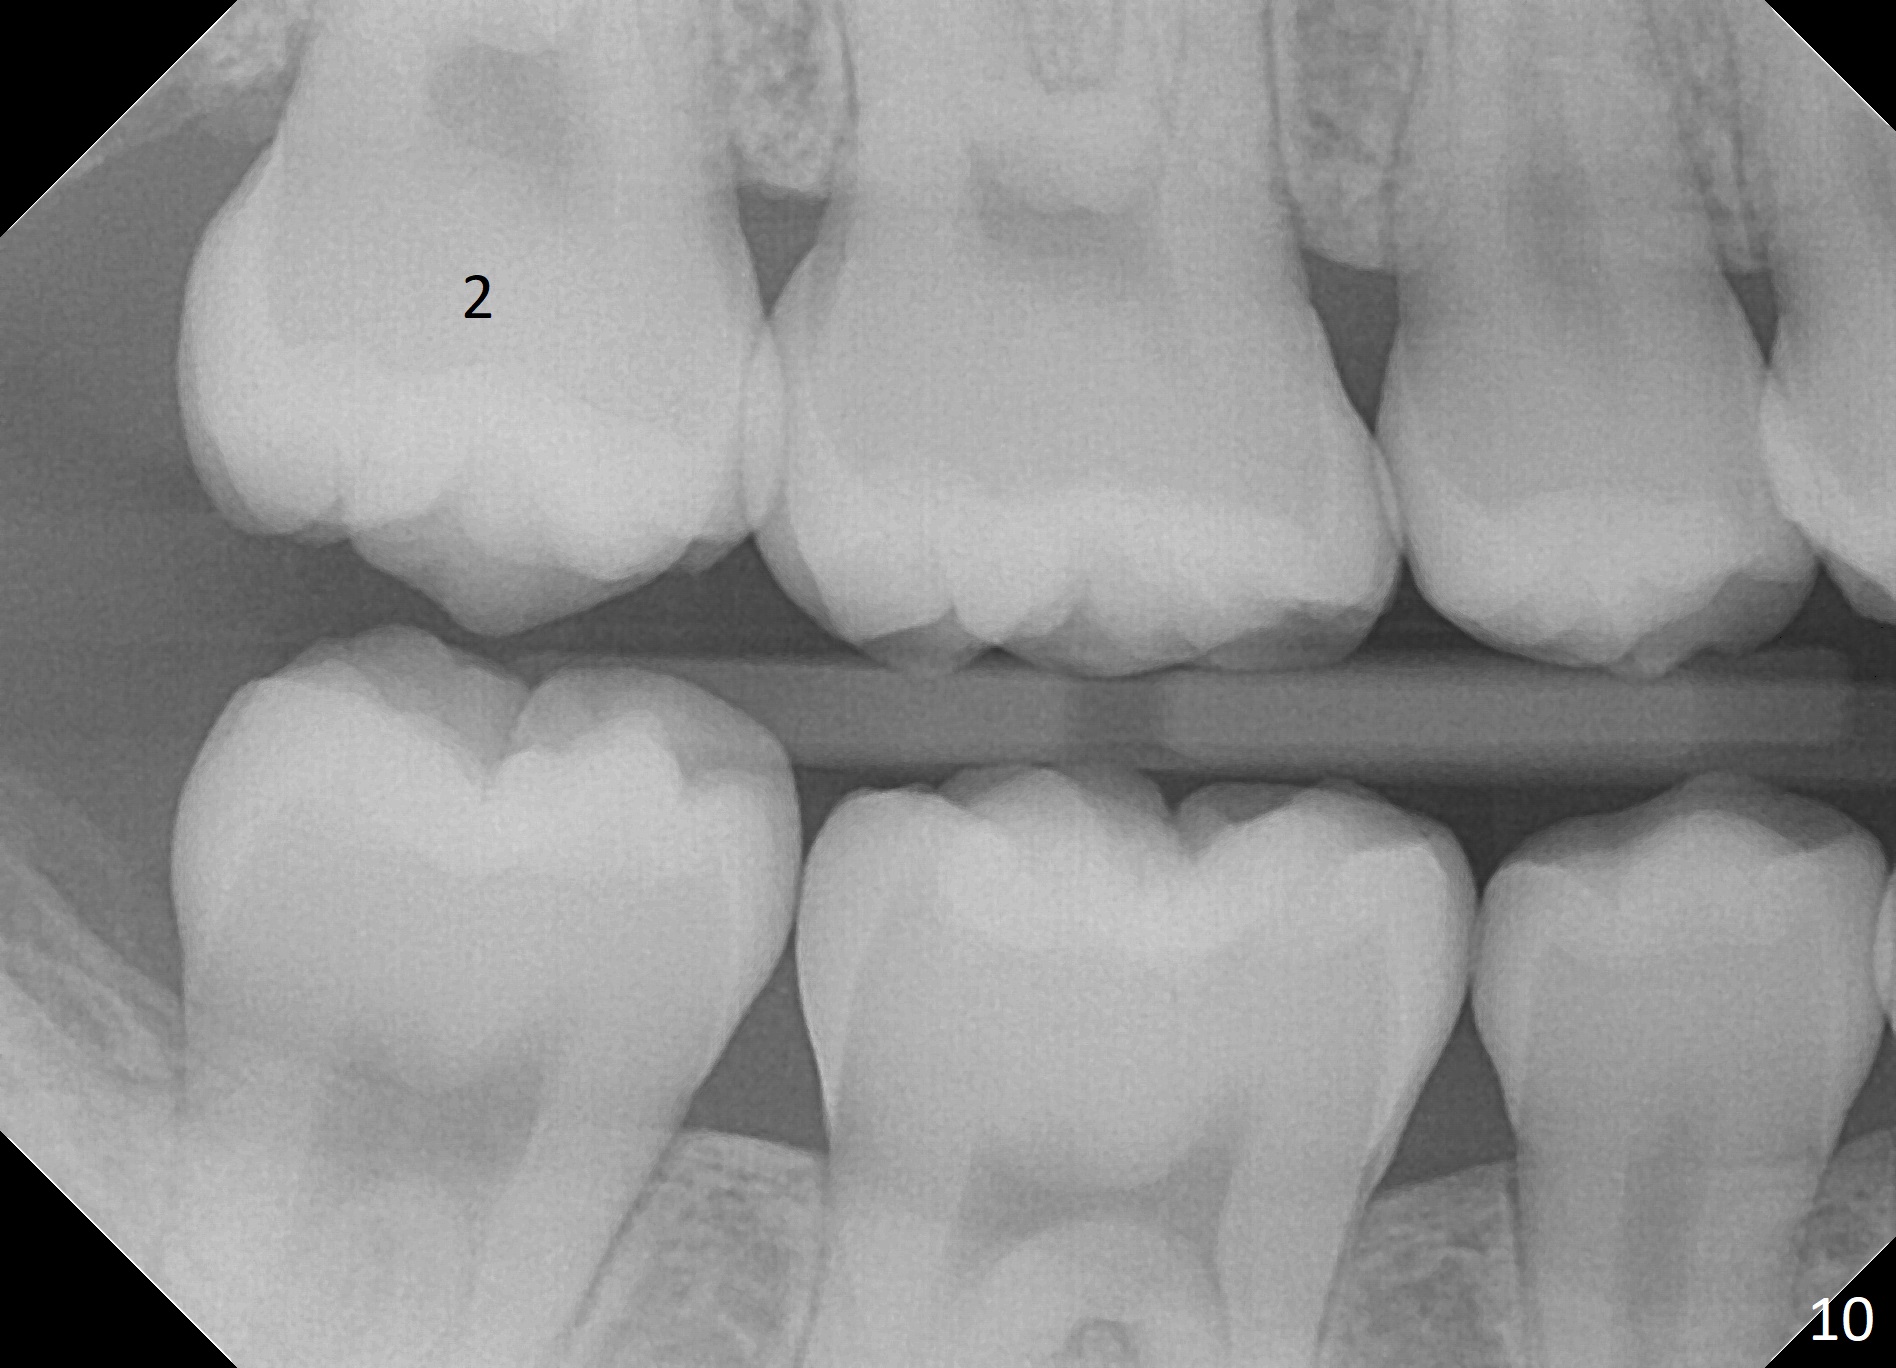

The distobuccal cusp of the tooth is subgingival 8 months post banding (Fig.6 (mirror view) *). A 2nd surgery is performed to expose the gold chain (Fig.7 <) and a bracket is placed. With arch wires, eruption of the impacted tooth is quickened (Fig.8). Later a 3rd minor surgery is done to place a lingual button to facilitate lingual cusp eruption. Finally a band has to be placed at #15. Treatment finishes in 2 years. The patient (15 years 2 months old) returns for follow up 3 months post debanding (Fig.9). There is no bone loss around the tooth #15 2 years 4 months post de-banding (Fig.11, as compared to the tooth #2 (Fig.10)).